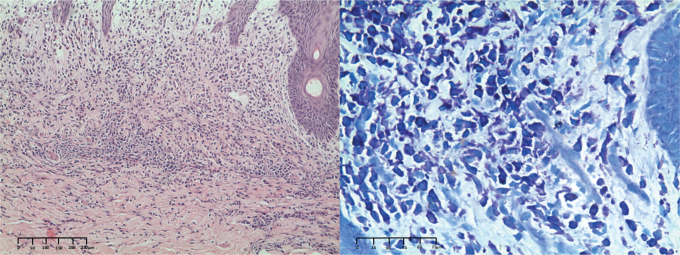

A 9-month-old Child with Diffuse Cutaneous Bullous Erythema: A Quiz.

一个9个月大的儿童弥漫性皮肤大疱性红斑:一个小测验。